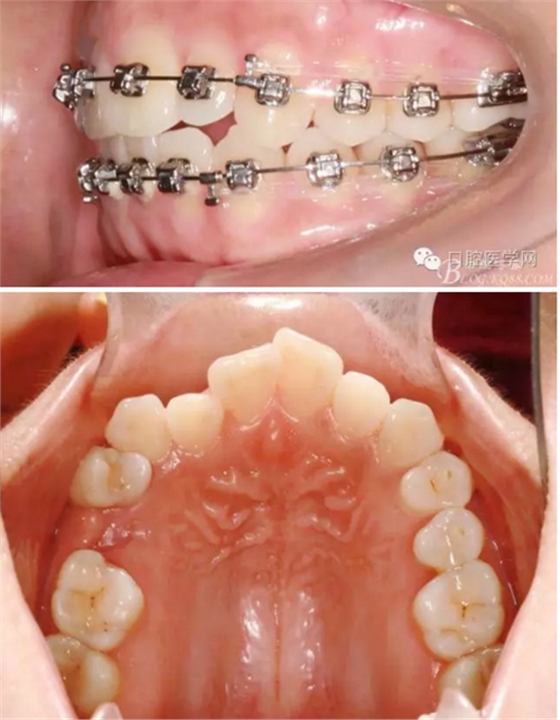

37,45缺失后,鄰牙近中移動(dòng)占據(jù)了部分牙位;患者要求減少治療費(fèi)用,不做種植修復(fù),那怎么協(xié)調(diào)右側(cè)的咬合關(guān)系?

15是根管治療過的牙齒,只好忍痛舍去......

在滿足功能的前提下,退而求其次...有時(shí)候,正畸醫(yī)生不得不妥協(xié)。